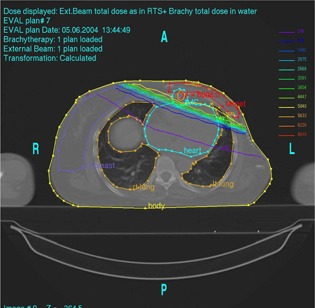

Figure 1 shows the isodose distribution in the axial plane for IMCBT and 3DCRT in PLATO EVAL module. The contribution from both the external and brachytherapy is displayed. Internal mammary chain was the target for brachytherapy, while the left breast was the target for external. Internal mammary chain was treated with HDR, while the left breast was treated with two parallel‐opposed conformal tangential 6‐MV photon beams with 15° wedges. Figure 2 shows the integral DVH for heart, lungs, coronary, and left IMC for IMCBT and 3DCRT with PLATO. Figure 3 shows the integral DVH for PTV and IMC for IMCBT and 3DCRT with PLATO. Internal mammary chain, as well as the left breast, was covered with the 95% isodose. Figure 4 shows the isodose distribution in the axial plane for IMRT in Cadplan. The isodose washes of 90%, 95%, and 108% are shown. The PTV here was the IMC included in the left breast. Five coplanar beams were placed with 6‐MV photons. Figure 5 shows the DVH for PTV, heart and both lungs for IMRT in Cadplan.

Figure 1.

Isodose distribution in the axial plane for IMCBT plus 3DCRT with PLATO. Internal mammary chain was treated with HDR brachytherapy irradiating the 2‐cm cylinder; the left breast was treated with two tangential conformal 6‐MV photons with 15° wedges. The combined dose distribution has been taken from the PLATO EVAL module.